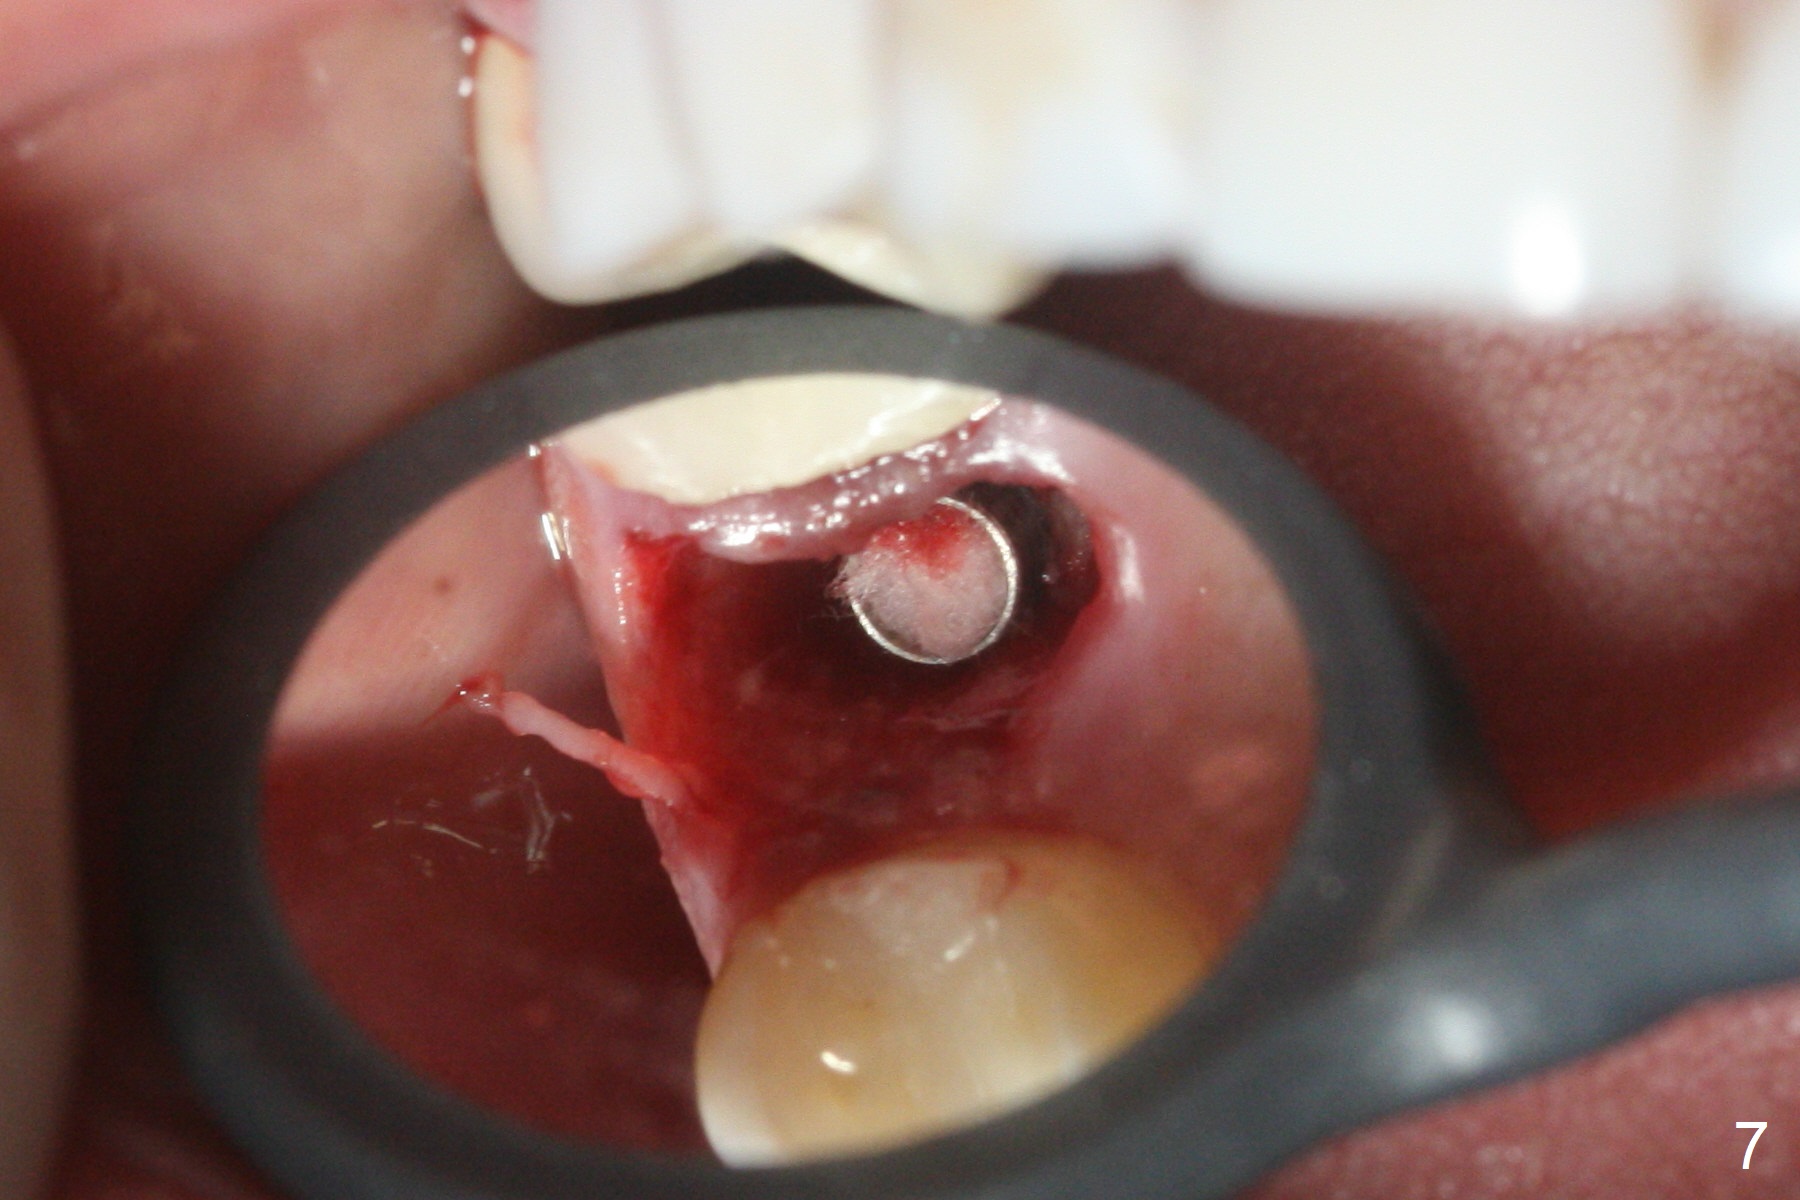

After extraction of the tooth #4 with palatally subgingival fracture (Fig.1 ^), white hard tissue is found in the socket, the density of which is hard (Fig.2 D). When osteotomy passes this portion of the bone (Fig.3 red dashed line), bone density feels reduced suddenly. The osteotomy is moved mesially slightly (Fig.4 (2.7 mm drill)). When a 3.8x15 mm dummy implant is placed with stability, there is an apical space (Fig.5 red dashed line). Therefore the final implant is longer (3.8x18 mm, <30 Ncm, Fig.6, 7). Vanilla graft is placed around the implant and a 4.5x4(4) mm abutment is placed immediately for an immediate provisional (Fig.8). Although the provisional easily dislodges in spite of remake, the implant seems osteointegrated with decreased space 4 months postop (Fig.9). The gingiva is healthy, although it covers the abutment margin partially. Gingivectomy appears necessary for impression.